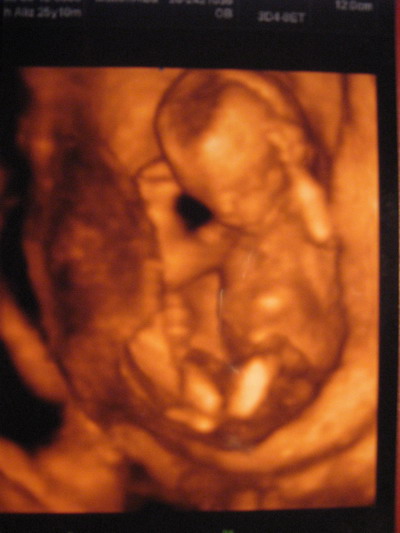

31 hetes